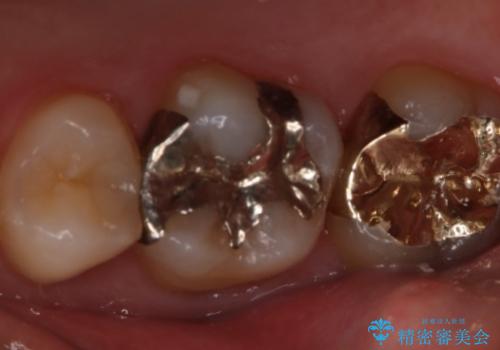

- 右上6番の銀歯のやりかえを希望し来院された患者様です。

切削量や形状からインレーでの治療を計画しました。

ご本人が金歯を希望されたため、ゴールドインレーでの治療を選択しました。